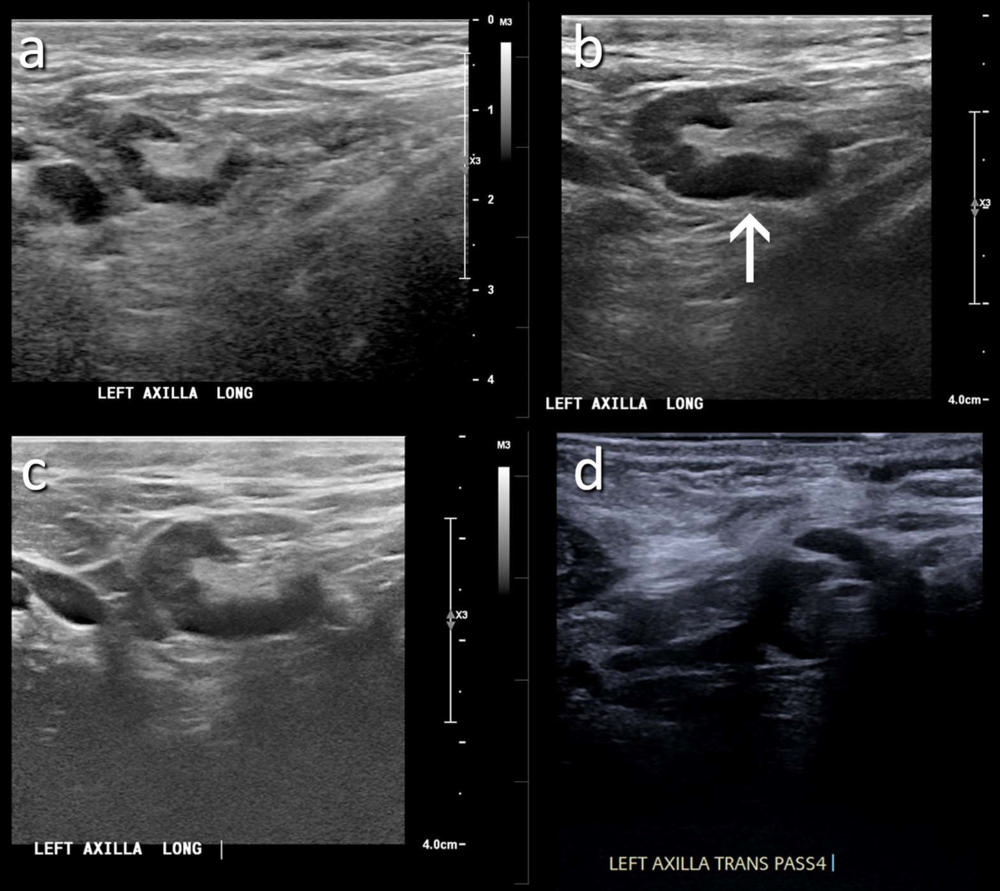

Figure 2. (A) A 46-year-old patient with a strong family history of breast cancer had a screening ultrasound prior to COVID-19 vaccination demonstrating a morphologically normal left axillary lymph node. (B) 25 days following the second dose of the COVID-19 vaccination, the patient presented with a palpable lump in the left axilla and ultrasound demonstrated enlarged lymph nodes with cortex measuring up to 6 mm in thickness (arrow). (C) A follow-up ultrasound 21 weeks following demonstrated stable axillary lymphadenopathy. (D) An ultrasound-guided core biopsy was then recommended and pathology demonstrated lymphoid cells negative for carcinoma.

High-res (TIF) version